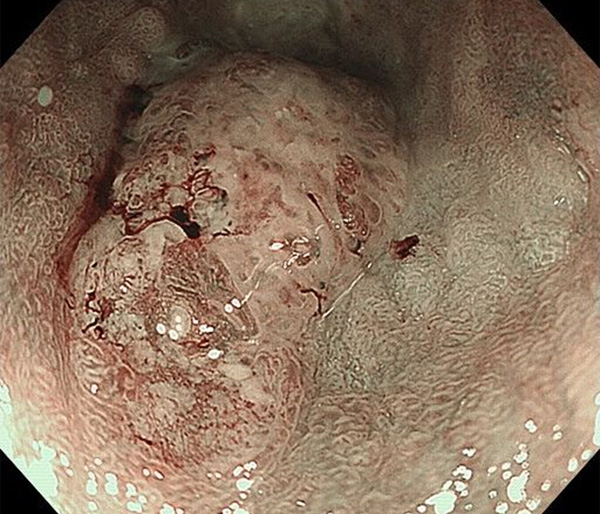

内視鏡所見と病理組織像の1対1対応が可能な症例を公募いたします。主にLSBEに発生した早期癌(HGDを含む)を対象としますが、興味深い症例であればSSBE癌でも結構です。採否は世話人へご一任ください。

特に、本邦では極めて稀なlong segment Barrett’s esophagus(LSBE)から発生した早期癌は、診断に難渋する場合も多く、欧米ではランダム生検による検出が標準的とされています。背景のBarrett食道もろとも全体を内視鏡切除+ラジオ波焼灼する欧米と異なり、ESDで内視鏡的な局所切除が基本の本邦では、存在診断+範囲診断(特に水平)を的確に行うことが不可欠です。

そのためには、一流の病理医による組織学的診断とエキスパート内視鏡医による拡大内視鏡像との一対一対応を徹底的に行うことで、『本来、見えないであろう拡大所見の先にある組織構築像が診えてくる』所まで内視鏡診断レベルを上げていく必要があります。その実現には、一対一対応を追究した症例(特にLSBE発生例)1例でも多く経験するしかありません。本研究会でBarrett食道腺癌(LSBE発生早期病変)を共に学び、拡大内視鏡像の一歩先を診るスキルを習得しましょう!一人でも多くの皆様のご参加をお待ちしています。

私は、Barrett食道癌はHGDも含め、内視鏡による存在診断、範囲診断が可能と信じて来ました。しかし最近、NBI拡大観察を併用しても側方範囲診断が不可能なLSBE症例を経験しました。診断技術を向上させるためには、多くの症例を診るしかありません。そこで、Barrett食道に造詣の深い先生方に世話人をお願いし、Barrett食道研究会を立ち上げることに致しました。全国からLSBE症例を集め、内視鏡的、組織学的診断に迫りたいと思います。皆様のご参加をお待ち致します。